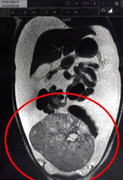

Mang khối u nang buồng trứng nặng 15kg nhưng một bệnh nhân lại bị nhầm có bầu 9 tháng.

Bị u buồng trứng nhưng không có tiền điều trị, chị D. về nhà uống thuốc nam nhưng tình hình ngày càng nặng, bụng mỗi lúc một to, khối u nặng tới 32kg.

Một cô gái đã mang khối u buồng trứng nặng 33kg, tương đương với 10 đứa trẻ sơ sinh trong suốt nhiều năm qua.